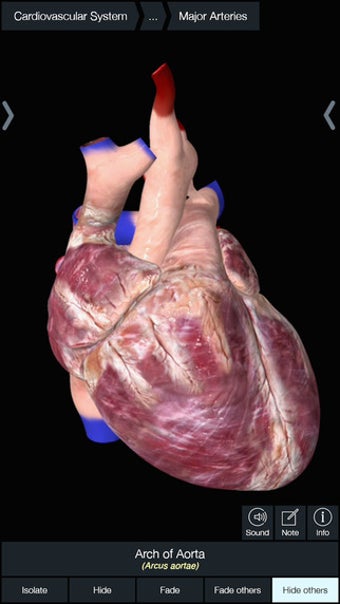

Essential Anatomy 3 ไม่ใช่การปฏิวัติในซีรีส์แอป Essential Anatomy แต่เพิ่มรายละเอียดและใช้งานง่ายขึ้น ไปที่แอป สิ่งที่น่าประทับใจที่สุดเกี่ยวกับ Essential Anatomy 3 คือ ระดับของรายละเอียดและโมเดล 3 มิติ ที่คุณสามารถจัดการและสำรวจได้ Essential Anatomy 3 ทำให้ไม่เปิดเผยอวัยวะหรือเอ็น - ระดับของรายละเอียดดีพอๆ กับสิ่งที่คุณพบในสารานุกรมทางการแพทย์

สำหรับนักศึกษาแพทย์โดยเฉพาะ Essential Anatomy เป็นเครื่องมืออ้างอิงที่ยอดเยี่ยม โมเดล 3 มิติช่วยให้คุณดูและตรวจสอบส่วนต่างๆ ของร่างกายมนุษย์ได้จากทุกมุม โดยให้รายละเอียดที่น่าทึ่งซึ่งปกติแล้วคุณจะสัมผัสได้ผ่านการผ่าเท่านั้น

หากคุณต้องการค้นหากระดูก อวัยวะที่เฉพาะเจาะจง หรือกล้ามเนื้อ คุณเพียงแค่ค้นหาตามส่วนต่างๆ ของร่างกาย แล้ว Essential Anatomy จะเน้นตรงจุดที่พวกเขาอยู่ด้วย คำอธิบายที่เป็นประโยชน์ของแต่ละส่วน สิ่งเดียวที่ขาดคือภาพเคลื่อนไหวของอวัยวะและกล้ามเนื้อในการทำงาน

Essential Anatomy ใช้งานง่ายมาก ฟังก์ชันการค้นหาคือสิ่งที่คุณต้องการมากที่สุดหากคุณกำลังเรียนอยู่ แม้ว่าคุณจะสนุกสนานไปกับการสำรวจและหมุนร่างกายก็ตาม คุณสามารถแยกชั้นของกล้ามเนื้อและเนื้อเยื่อออกเพื่อเผยให้เห็นสิ่งที่อยู่ภายใต้ ซึ่งจะช่วยให้คุณมีความคิดที่ดีขึ้นมากเกี่ยวกับการทำงานของร่างกาย มากกว่าที่จะอ่านมันในหนังสือ

นอกจากนั้น ยังมี เครื่องมือบุ๊กมาร์ก หากคุณต้องการบันทึกเฉพาะส่วนที่ต้องการย้อนกลับไปดูในภายหลัง และคุณสามารถแยกมุมมองร่างกายตามประเภทของชิ้นส่วน (เช่น กล้ามเนื้อ หลอดเลือดแดง เส้นเลือด ฯลฯ)